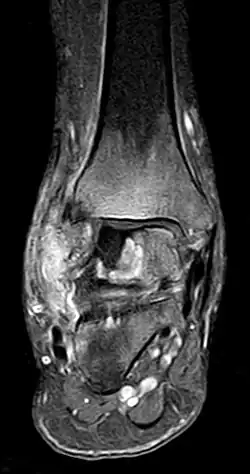

- Stadium ARCO 0

Im Anfangsstadium sind in konventionellen Röntgenaufnahme keine krankhaften Veränderungen zu erkennen. In seltenen Fällen ist eine dezente Auflockerung der Knochenfeinstruktur (Trabekel) in dem betroffenen Areal zu erkennen: das Ausmaß dieser Auflockerung ist jedoch zumeist so gering, dass es nicht sicher erkannt werden kann. In der Kernspintomographie (MRT) ist in diesem Stadium ein Bild analog dem Knochenmarködem (KMÖ, transiente Osteoporose; bone marrow edema, BME) zu erkennen. Unter Verwendung der short tau inversion recovery (STIR) Aufnahmesequenz wird eine Signalhyperintensität (helles Aufleuchten im Graustufen-Kernspinbild) festgestellt (vergleiche Bild 1a und 2 helle Ränder). Eine sichere Unterscheidung zwischen dem prinzipiell reversiblen Bild eines KMÖ/BME und dem Stadium ARCO I einer aseptischen Knochennekrose ist nicht mittels des Kernspintomogramms möglich.

- Stadium ARCO 1

Reversibles Frühstadium (MRT-positiv/reaktive Randzone)

- Stadium ARCO 2

Irreversibles Frühstadium (Röntgen positiv)

_-_MR_Coronal_STIR_-_child_13_yrs_after_ALL_-_01.jpg)